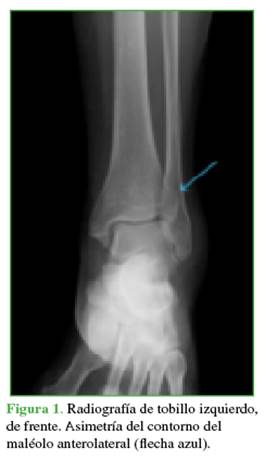

Paciente de 62 años, ama de casa, previamente independiente para sus actividades de autocuidado y funciones del hogar, con diabetes mellitus tipo 2 no insulinodependiente, hipertensión arterial controlada y hallux valgus bilateral asintomático. Acudió al Servicio de Urgencias de nuestra institución luego de un trauma en inversión al bajar un escalón, tras lo cual refirió dolor, edema, limitación para la bipedestación y la marcha. Tenía dolor a la palpación del cuello del pie, movilización espontánea de los dedos y pulso pedio palpable simétrico, no se observaron deformidades ni heridas. Ingresó para la toma de radiografías anteroposterior y lateral del tobillo derecho, que revelaron una asimetría en la unión tibio-peronea y pérdida en la continuidad articular tibial (Figuras 1 y 2).